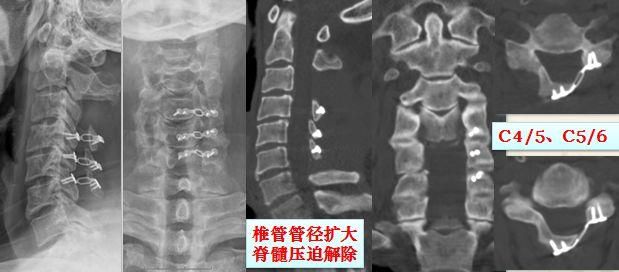

五、我院原创精准微创颈椎后路椎板开门成形术,适用于颈椎椎管狭窄导致的脊髓神经压迫患者。

典型案例

禤某,男,40岁,车祸致全身疼痛、乏力2天,诊断为1. 颈脊髓损伤;2. 颈椎管狭窄症(发育性颈椎管狭窄)。

术前X线、CT、MRI提示颈4-5平面脊髓挫伤、发育性椎管狭窄。

行我院原创改良颈3椎板切除、颈7头侧半椎板切除+颈4、5、6椎板单开门成形术后,症状明显缓解。